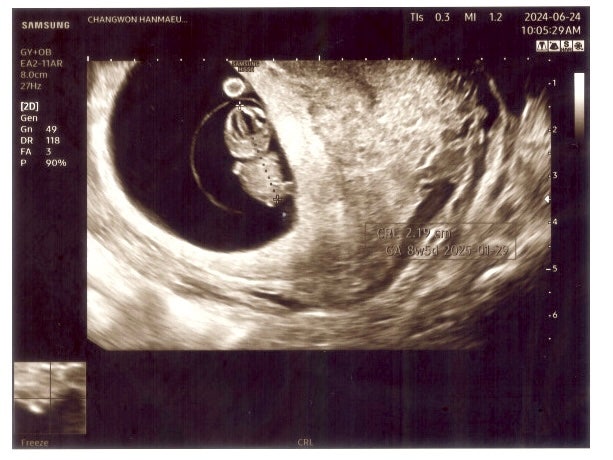

임신 8w5d / 2등신 젤리곰 / 입덧 / 창원한마음병원

이사 후 울산에서 며칠 지낸 뒤 창원 친정으로 내려와서 일주일 정도 보내고 있다. 창원에 내려오니 마음에...